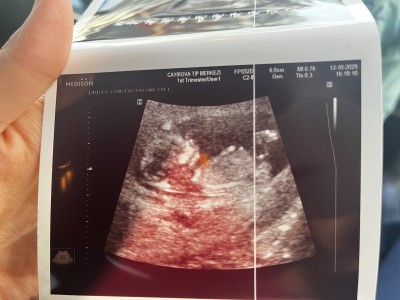

Kızlar 11+

imageKızlar 11+4 teyiz doktor çok erken dedi ama bir tahminim var dedi sizin var mı anlayan varsa yorumlayabilir mi

Gebelik haftası 11+4

İlk fotoda mı öyle hissettin 2. De mi bende ilkte kız ikincide erkeğe benzettim amin inşallah